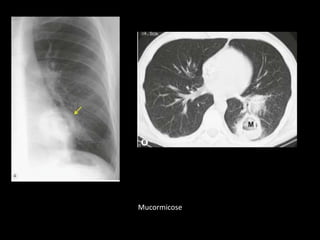

Mucormicose

Aspergilose broncopulmonar invasiva Radiografias: múltiplos nódulos periféricos, mal definidos que medem de 1 a 3 cm de tamanho e gradualmente coalescem em massas maiores ou áreas de consolidação. Um achado precoce na TC é a borda de opacidade em vidro fosco que circunda nódulos(sinal do halo na TC): o halo representa hemorragia ao redor de uma área focal de infarto pulmonar causado pelo Aspergillus, que invade os vasos pulmonares. Halo: outras infecções, TB, mucormicose, MTX hemorrágica e Wegener.